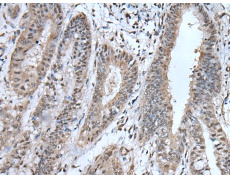

IHC positive control: |

Human liver cancer and human breast cancer |

IHC Recommend dilution: |

40-200 |